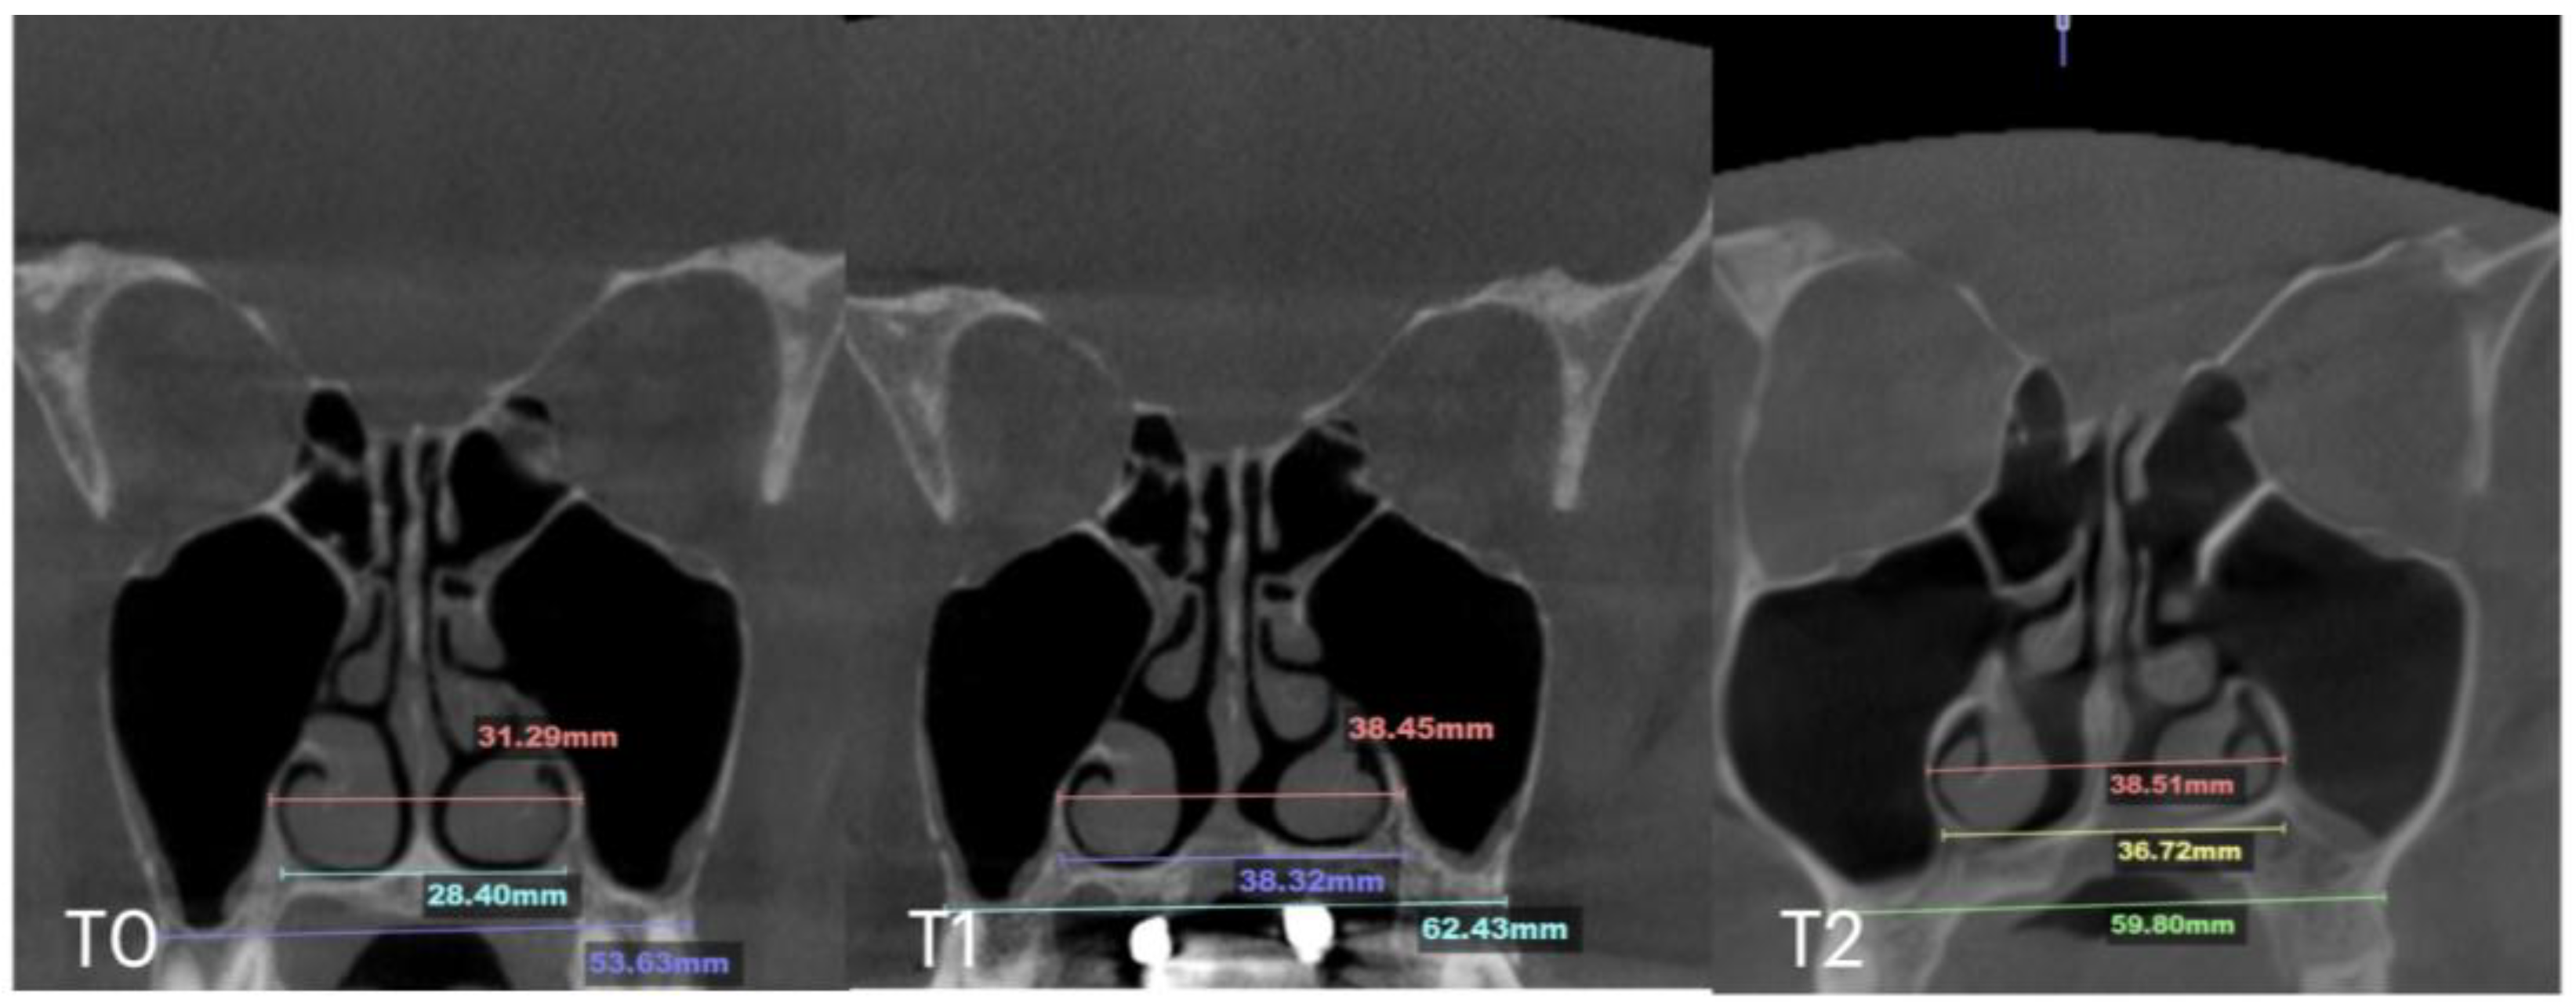

| Case C | 28.40 | 38.32 | 36.72 | 53.63 | 62.43 | 59.80 | 31.29 | 38.45 | 38.51 | 29.15 | 35.8 | 35.36 | 8.47 |